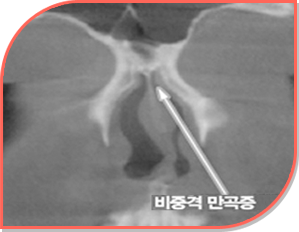

휜코는 코뼈나 비중격(코 중앙 연골)이 한쪽으로 치우치면서 모양이 비대칭이 되는 상태입니다.겉모양뿐 아니라,...

휜 코는 코가 좌우로 비대칭인 상태로, 외형적으로 눈에 띌 뿐만 아니라 호흡에도 영향을 줄 수 있는 문제인데요.간혹 ...